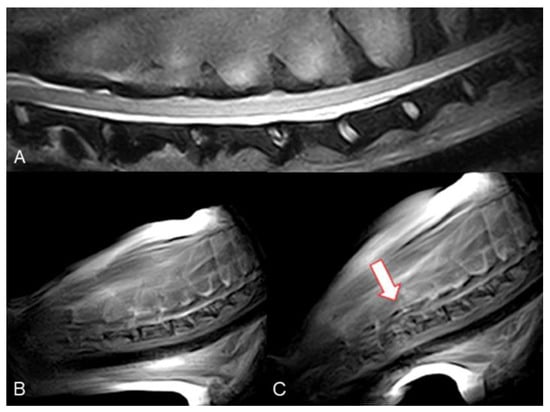

Figure 3. Dobermann, 8 years old, male entire (Case 7). Cervical spine MRI sample images: (A) T2 weighted mid-sagittal image of the cervical spine. (BE) Real-time kMRI during neck flexion, C4–C5 mild dynamic subluxation is visible (arrows).